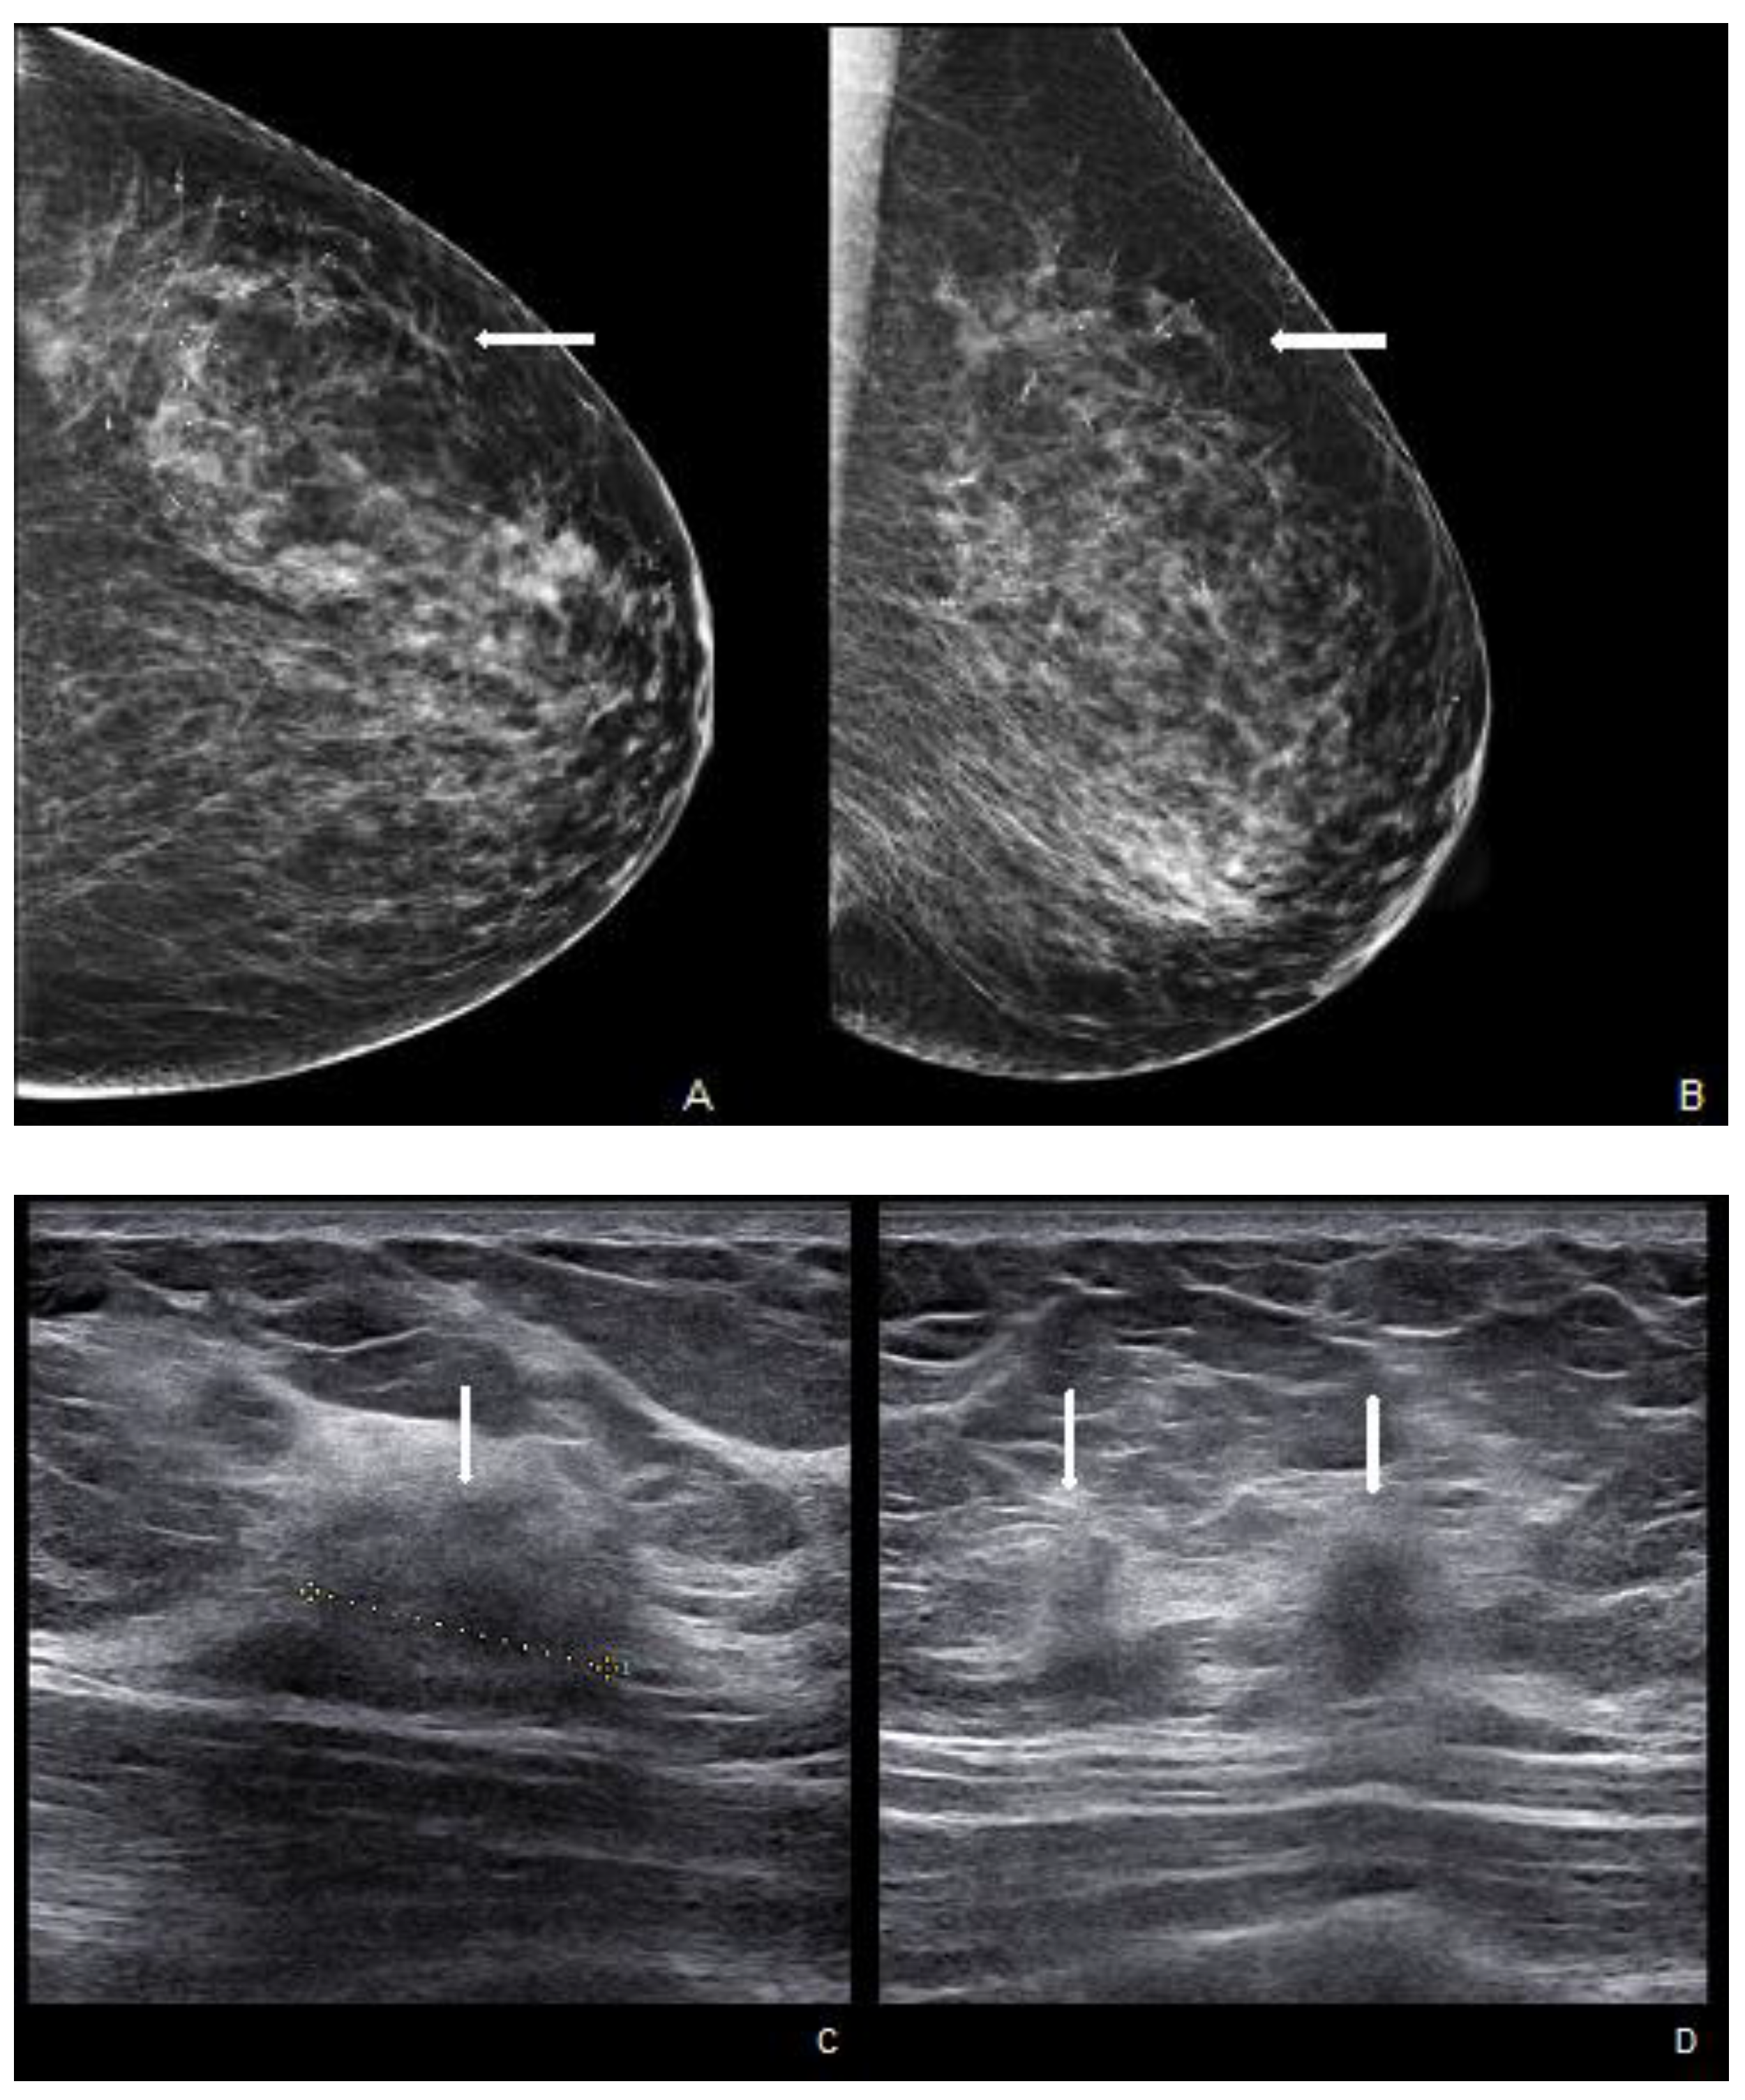

A careful and timely evaluation, including clinical examination with imaging techniques integration (as DM, US, and MRI), is always required in all patients with NAC skin changes to exclude MPD. However, a conclusive diagnosis invariably necessitates histological scrutiny. In addition to the typical clinical skin features, a thorough clinical breast examination is essential for detecting potential masses and axillary lymphadenopathy, which are indicators of underlying infiltrative pathology [45]. Specific imaging patterns have also been documented. A thorough mammographic assessment needs a digital system with an integrated tomosynthesis technique and magnification views of the NAC and the breast anterior third for detecting any underlying lesions and ruling out multifocal disease, as MPD has reported prevalence rates of 41% and 34% for multifocality and multicentricity, respectively [46]. Notable DM findings include thickening cutaneous or nipple and periareolar skin retraction [15]. Malignant microcalcifications along with a subareolar mass may be present, limited to the retroareolar region or elsewhere in the breast (Figure 4). However, DM sensitivity and specificity are limited: abnormal mammographic findings involving the NAC are not specific for MPD, especially in women with prior surgery or RT; in addition, DM may appear negative in 22–25% of patients, leading to a potential underestimation of disease extent [41,47].

Figure 4.

Woman with a bilateral breast augmentation and a history of recurrent eczema of the right nipple. A skin biopsy was performed, and MPD was confirmed. Unilateral craniocaudal (A) and oblique (B) mammograms of the right breast show periareolar skin thickening and diffuse fine pleomorphic microcalcifications (arrow). The patient underwent a stereotactic biopsy and was diagnosed with high-grade in situ ductal carcinoma.